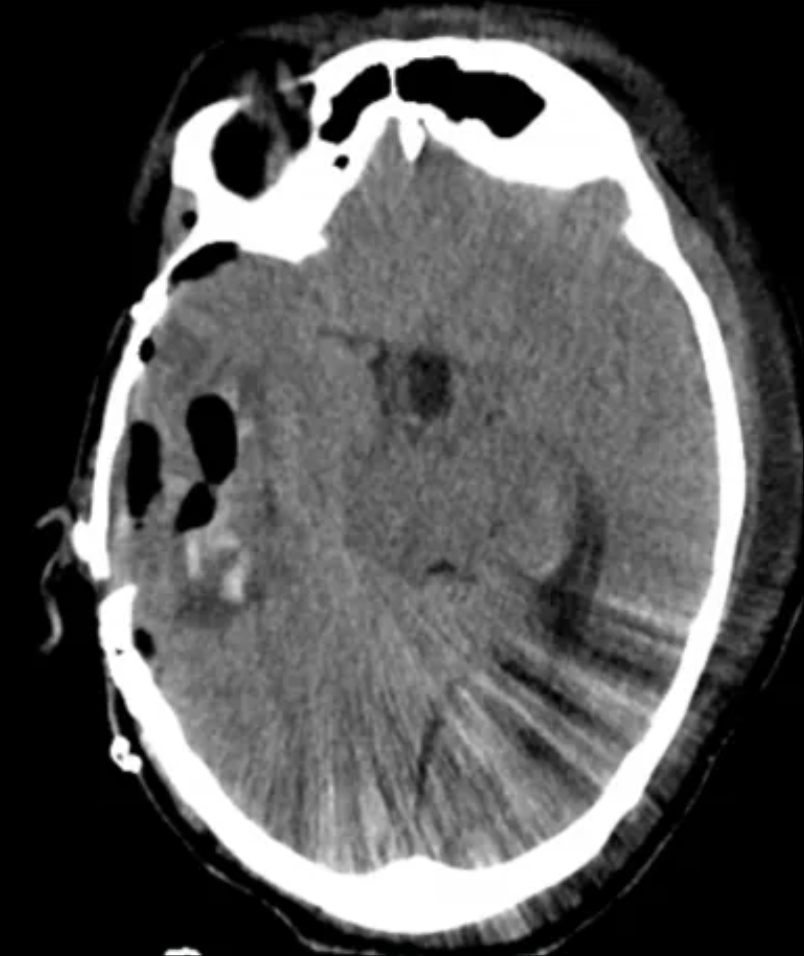

在经过一周的病情稳定后,第二场巨大颅内外沟通瘤切除术正式开启,神经外科团队挑战核心难点。这场手术从清晨8点持续至次日8点,整整24个小时!

在神经导航系统、神经电生理监测、内镜等尖端设备辅助下,高亮教授将该巨大肿瘤分区、分块,从脆弱的脑干和神经上小心翼翼剥离。

肿瘤已成功切除

青海藏族同胞扎西在术后恢复良好,现已出院返乡接受后续的康复治疗。医院建立了长期随访机制,持续跟踪患者预后。